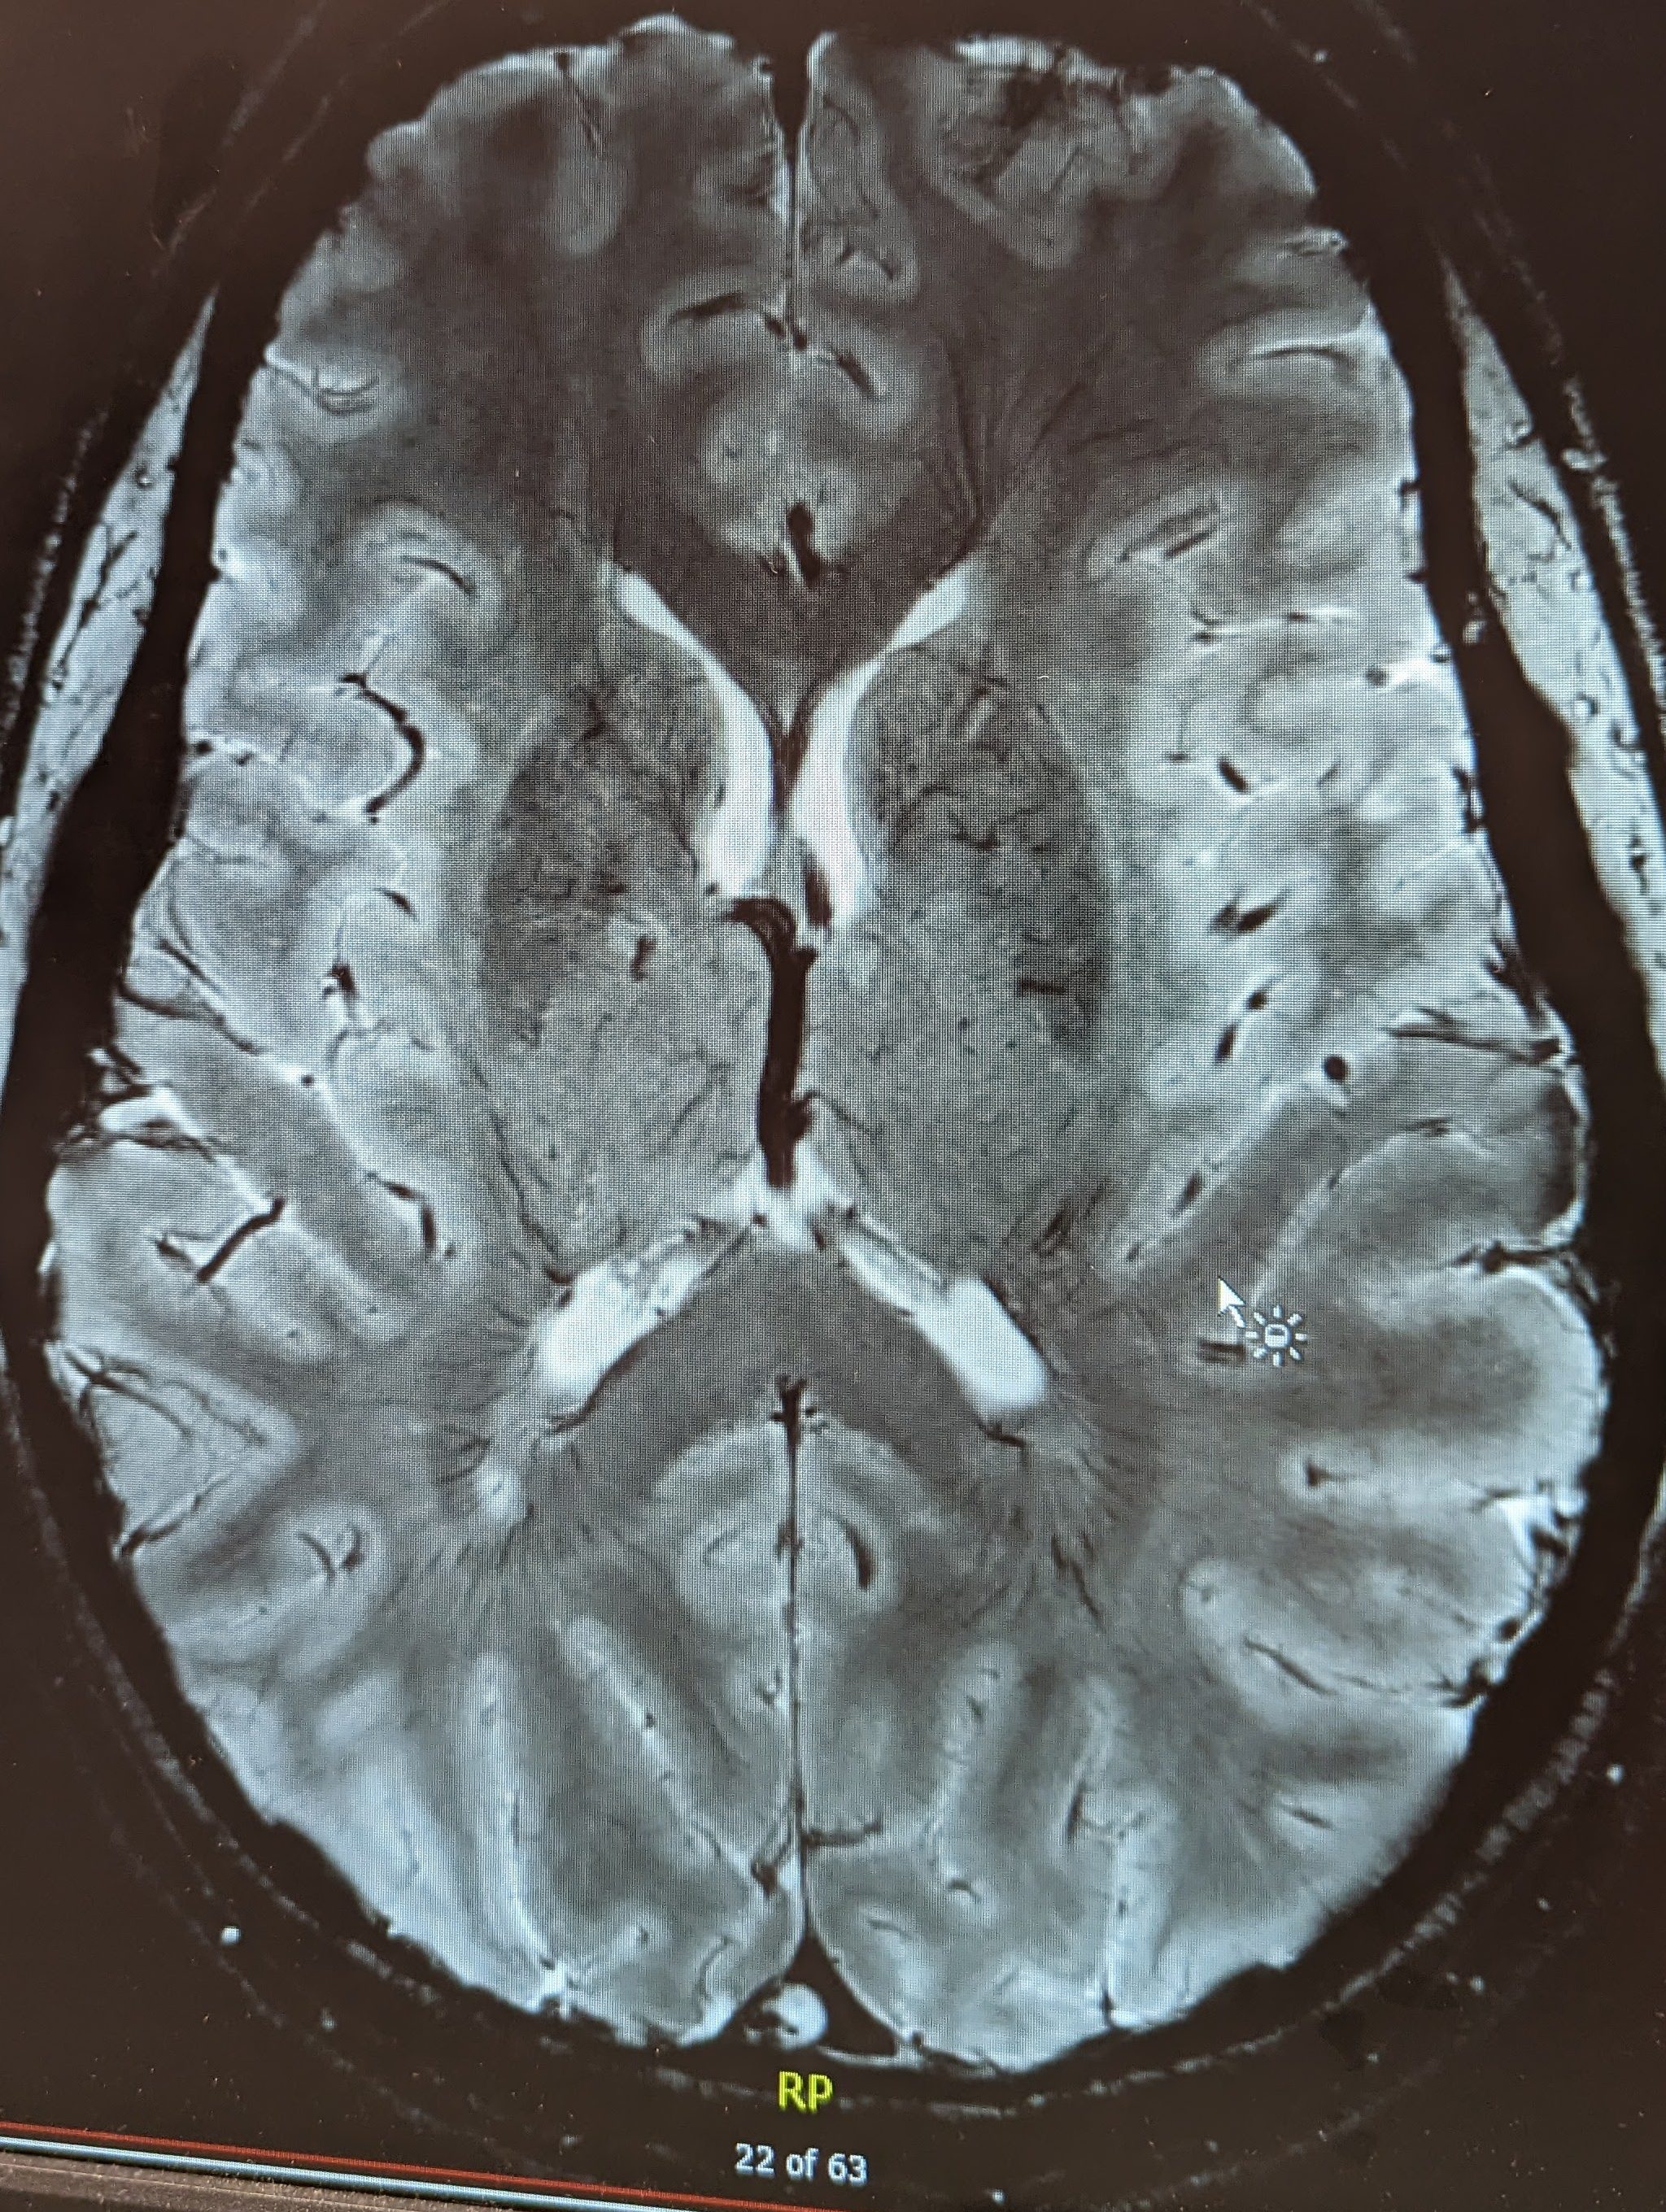

- 7T MRI & Research for MS

- Update on the 7T MRI